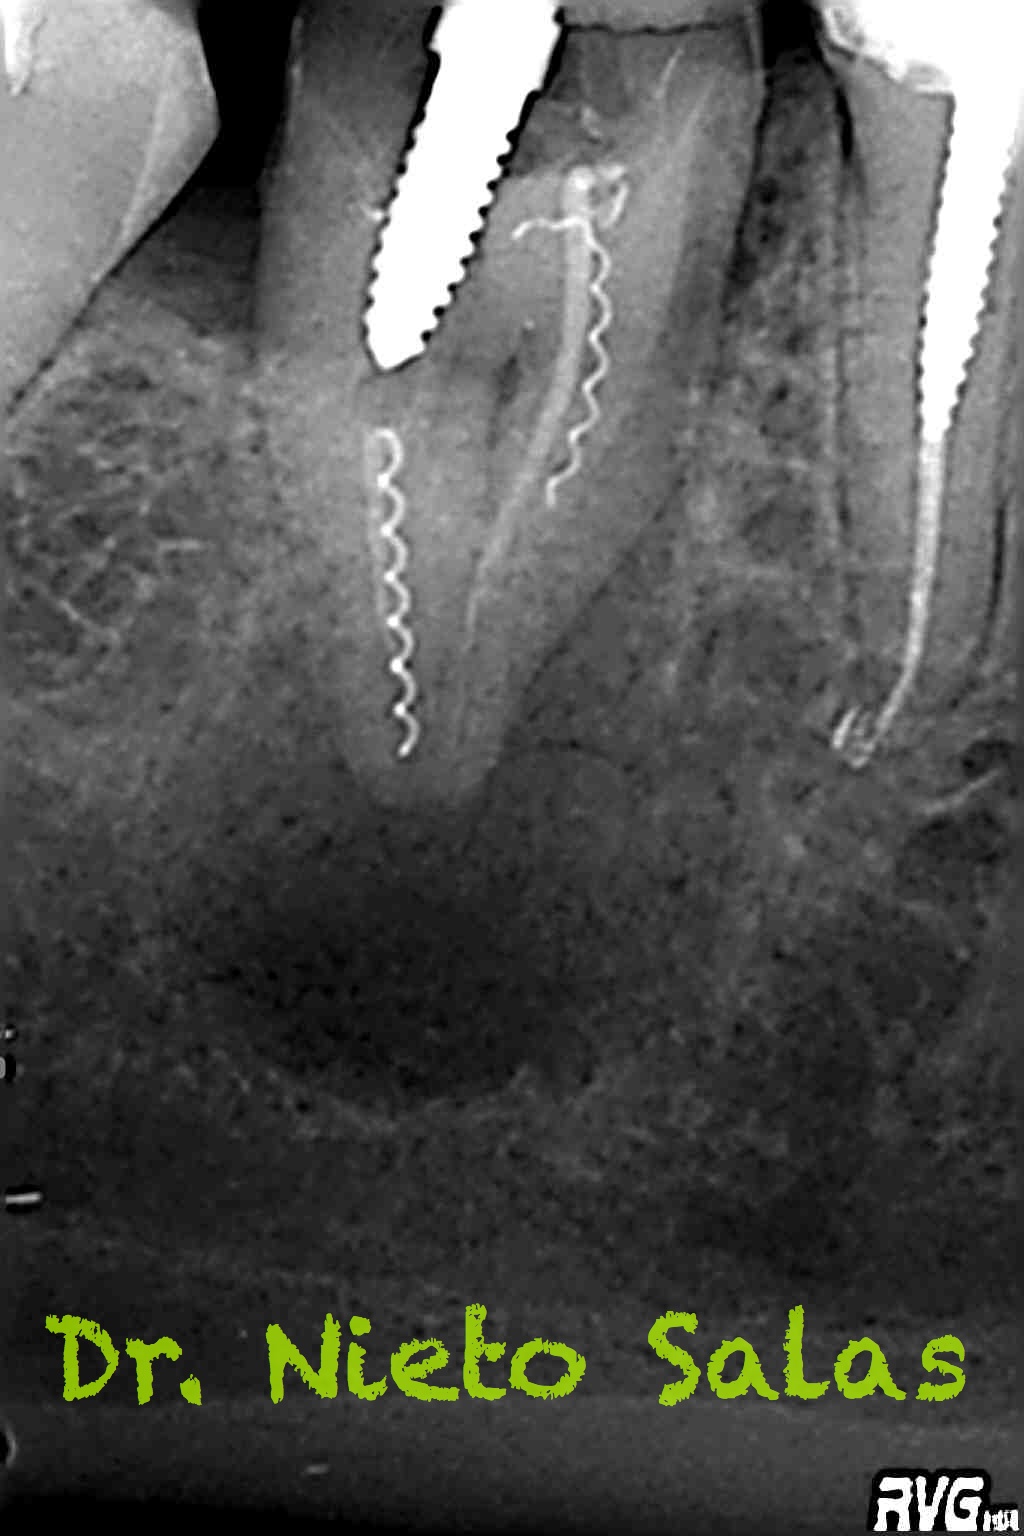

Nos remiten a la clínica a una paciente con un tratamiento previo de endodóncia realizado ya hace unos 5 años y que presenta una agudización del proceso. Se trata de un fracaso endodoncico por una falta de sellado tanto coronal como apical, en el que en el espacio intra-conductos nos encontramos dos léntulos, y en el acceso a los mismos un perno prefabricado.

Los puntos fuertes serán la retirado del perno y de los léntulos, a priori, no muy complicado, pero todo puede cambiar dentro de los conductos. Nuestro objetivo en la primera sesión será llegar a determinar la longitud de trabajo de los diferentes conductos, conformarlos y colocar nuestro Hidróxido de Calcio.

Con respecto al caso, bueno ya sabrás que trabajando con mágnificación, hay cosas que son más fáciles de lo que parecen, y con ultrasonidos, microdebraiders y paciencia todo salió bastante fácil.

Dentro de los ultrasonidos, removí el perno con una ET20 de Satelec y ProUltra nº4 y ET25 para los léntulos.

Presentaba un sistema de conductos en el que el conducto distal era acintado y los mesiales podían unirse después de instrumentarlos.